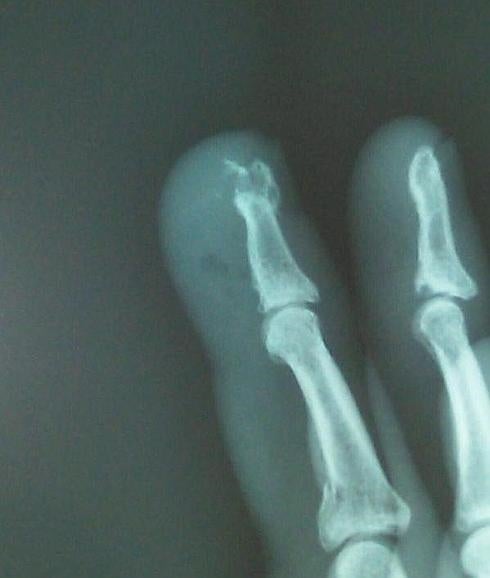

Radiografía que muestra la fractura del dedo de Irujo

En concreto, el pelotari de Ibero sufre una "fractura conminuta en la falange distal del tercer dedo de su mano derecha", según detectó el estudio radiológico efectuado en la Clínica San Miguel de Pamplona. Dicho dedo, añade el parte médico, se ha inmovilizado con una férula.